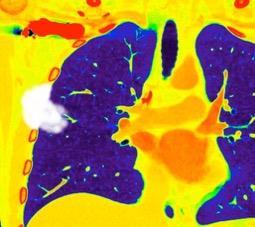

Nódulo en língula.

2005. Masa pulmonar.